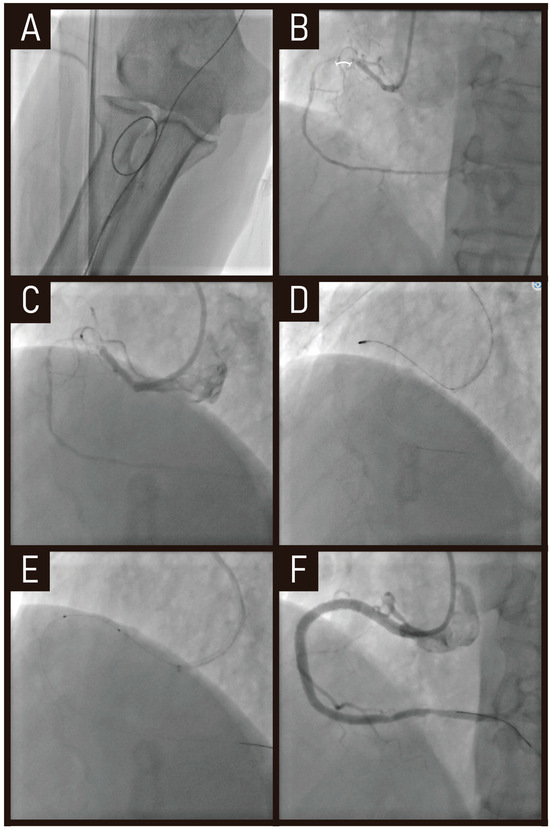

7.1. Case

7.2. Clinical Evidences of Drug-Coated Balloon in De Novo Small Coronary Vessels

7.3. Clinical Outcomes of RA Co-Treated with Drug-Coated Balloon in De Novo Small Vessel Coronary Lesions